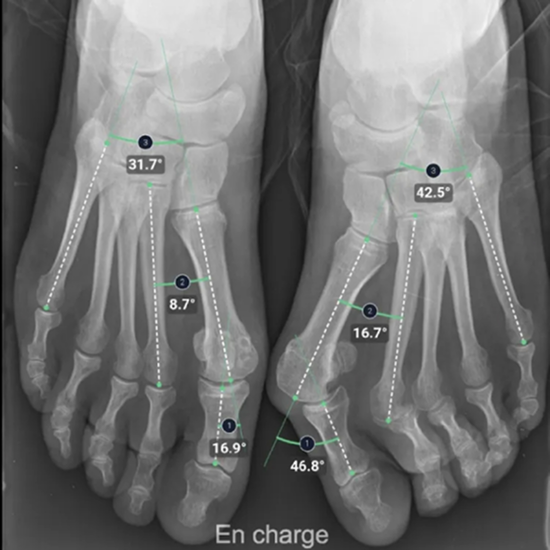

BoneMetrics: Automation of MSK Measurements and Workflow Optimization

With the aid of BoneMetrics, the capture of MSK measurements can be automated. Moreover, workflow optimization can be achieved through unparalleled precision in X-ray and EOS acquisitions.

BoneMetrics automatically performs standard measurements for the feet, legs, pelvis/hips, and spine.

Through accurate point placement and easily understandable displays, the introduction of the software allows you to direct your attention to more critical tasks.